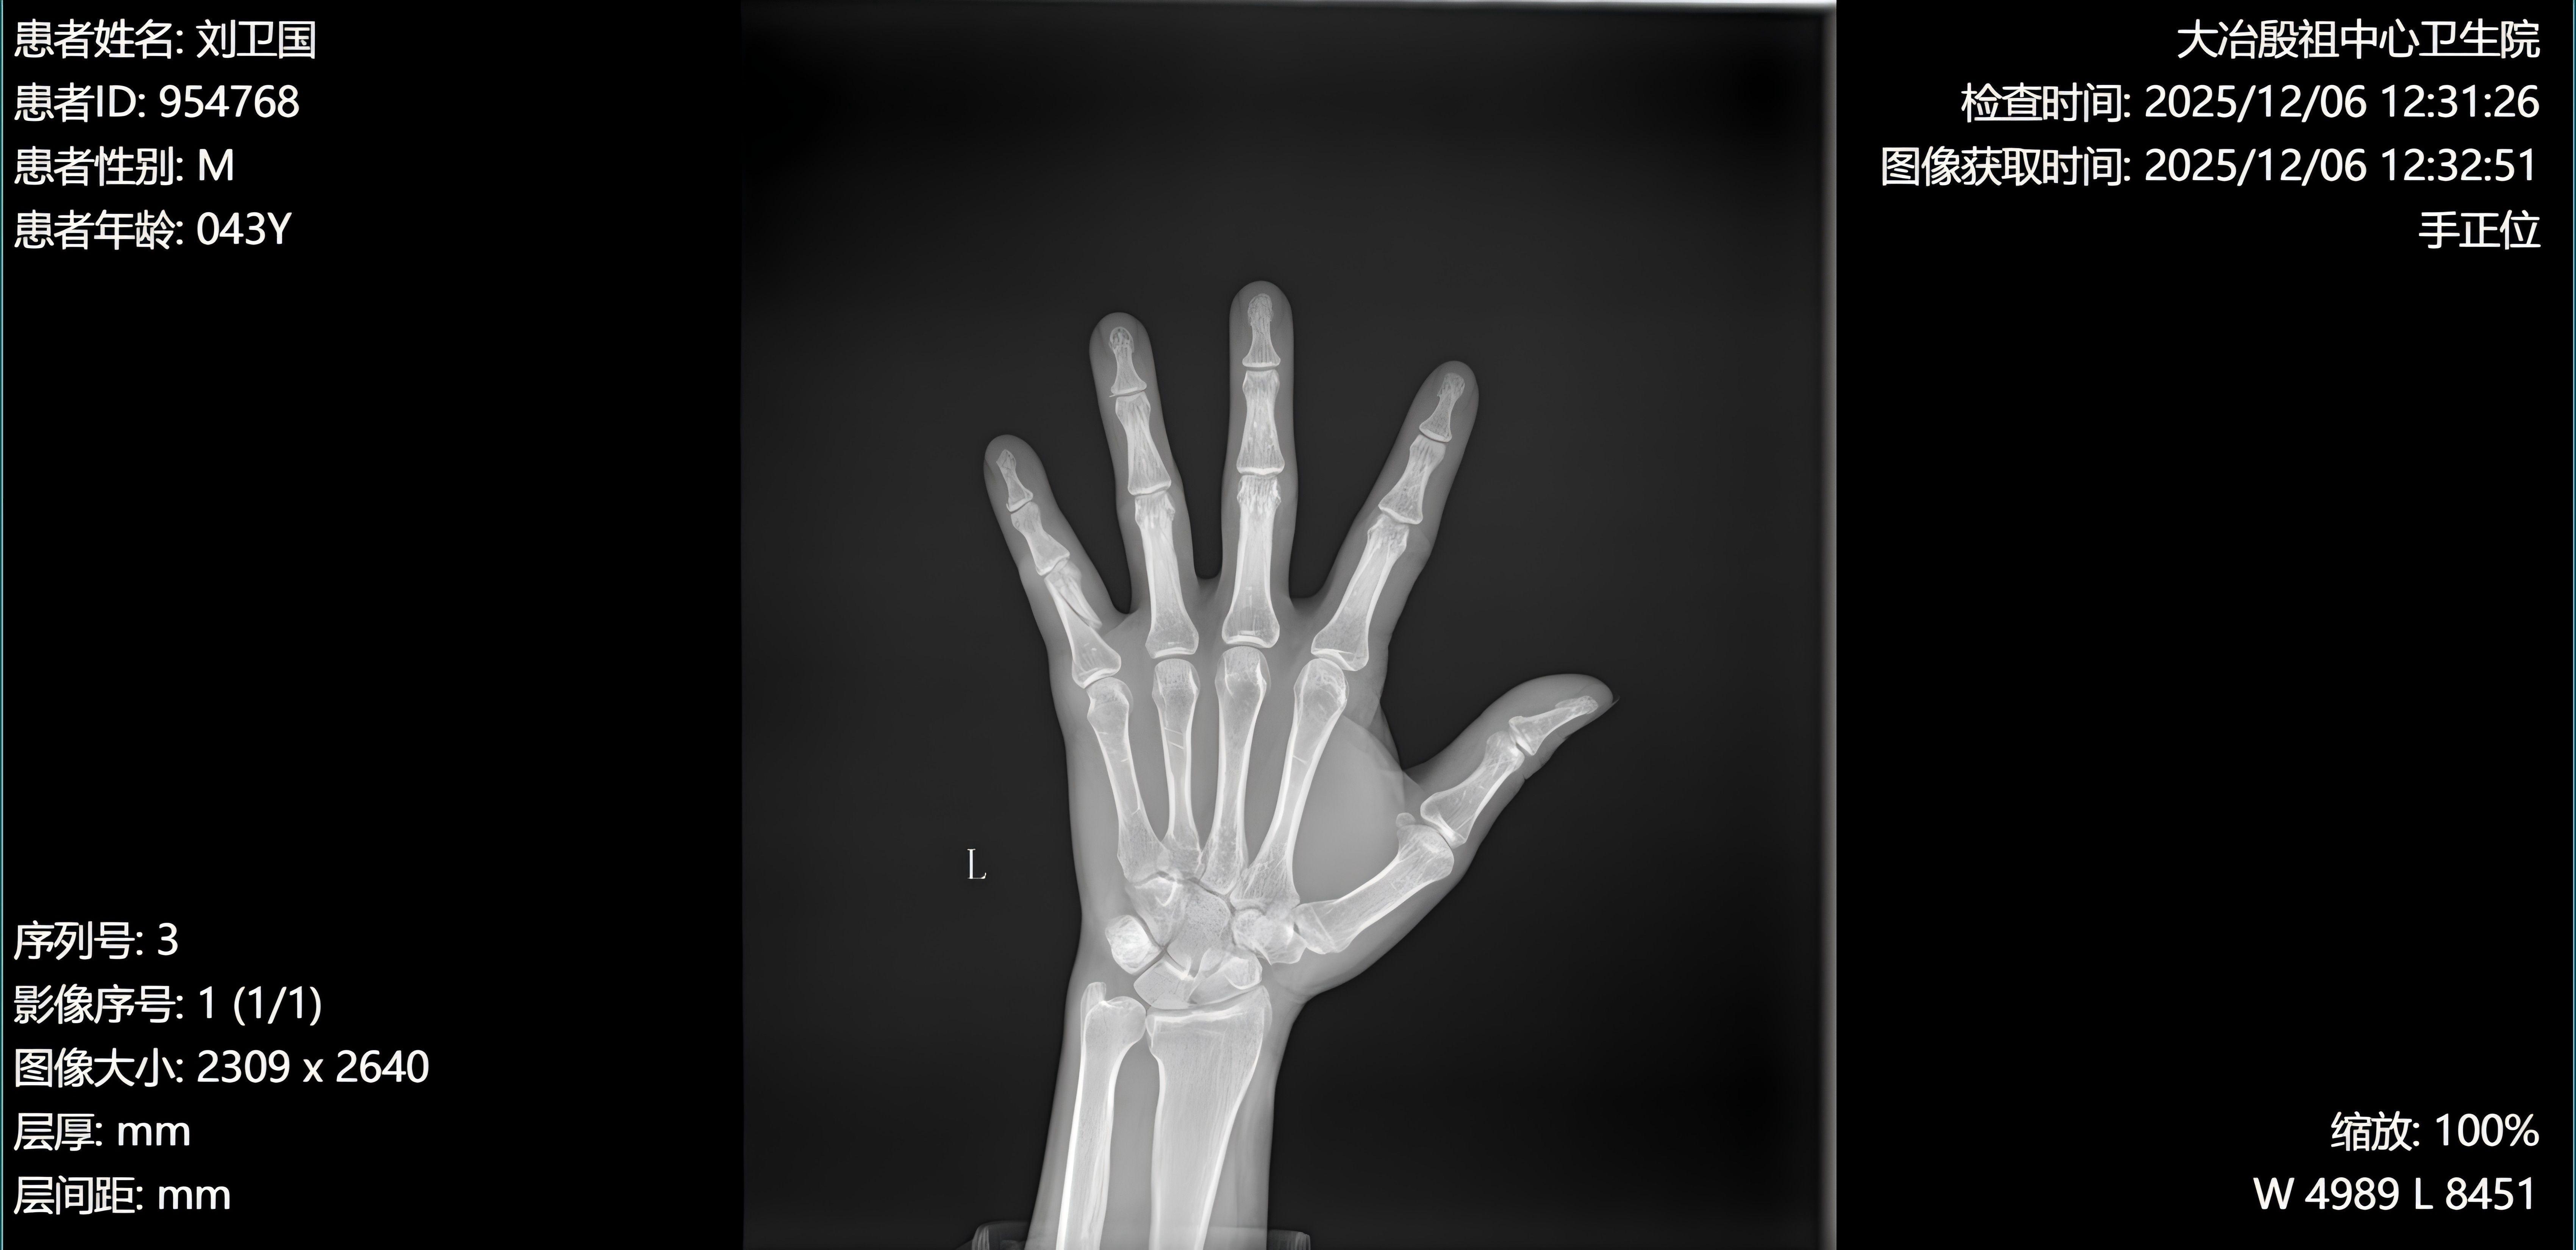

左手第 5 近节指骨骨?

患者男性,43岁

左手第5指外伤后疼痛、肿胀、活动受限1小时。

患者于一小时前因牵羊受伤,不慎被羊牵拉扭伤致左手第5指受伤,当即感局部剧烈疼痛,呈持续性锐痛,迅速出现肿胀,手指屈伸活动明显受限,无法正常抓握。伤后未行特殊处理,为进一步诊治来我处门诊。自受伤以来,患者精神尚可,无头晕、头痛、恶心、呕吐等全身不适,饮食、睡眠稍受影响,大小便正常。

一般情况:神志清楚,精神可,自主体位,查体合作,全身皮肤黏膜无黄染,浅表淋巴结未触及肿大。左手第 5 指近节明显肿胀,局部皮肤青紫,压痛显著,可触及骨擦感及异常活动,主动及被动屈伸功能受限,末梢血运、感觉正常,其余手指活动、感觉及血运均无异常。